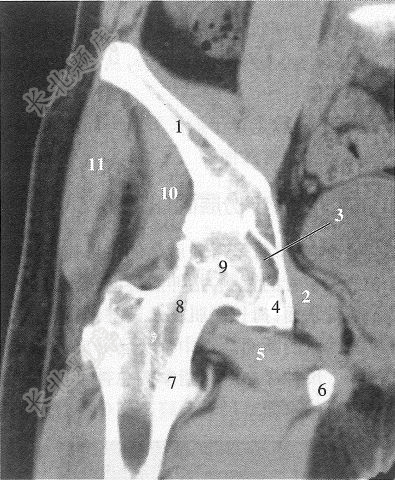

经股骨头后部的冠状断层上,图注11所标注的解剖结构是()

A、闭孔内肌

B、股骨头韧带

C、闭孔外肌

D、臀中肌

E、臀小肌